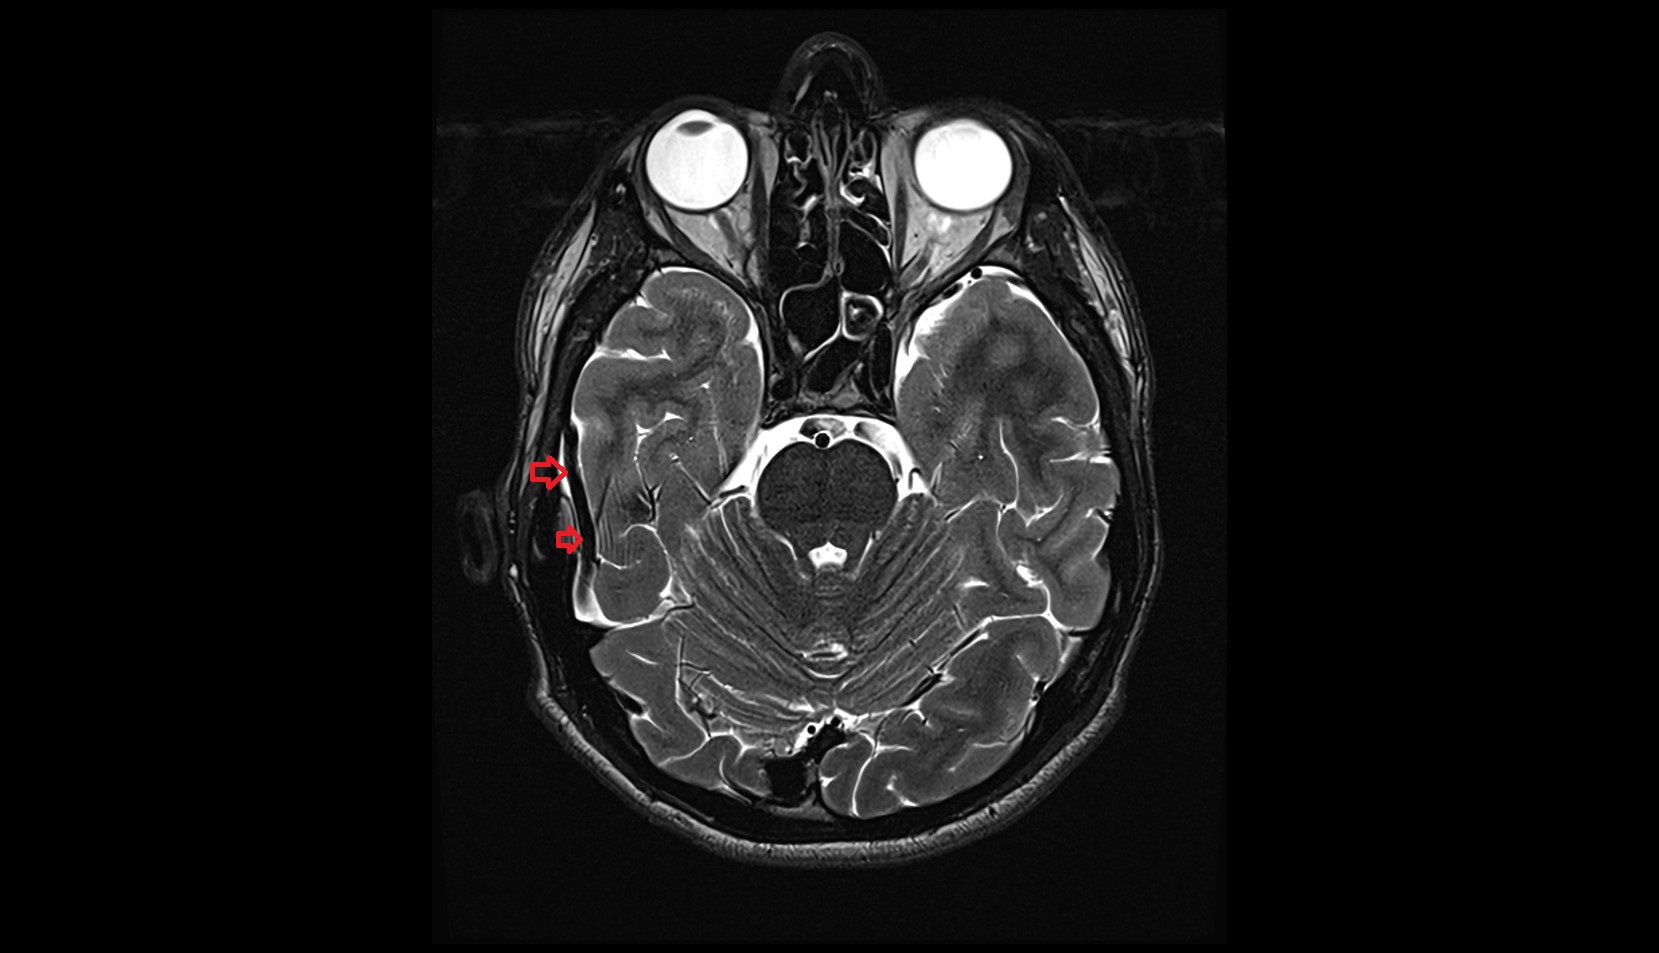

Inferior anastomotic vein (Labbé) MRI 3T axiall image